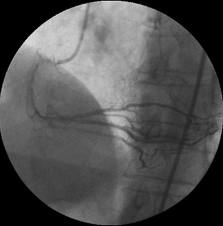

Contrastfoto die collaterale circulatie laat zien: Een slagaderlijke vernauwing wordt van de andere kant van bloed voorzien. Hierdoor wordt het weefsel van zuurstof voorzien en treden er geen of slechts geringe symptomen op.